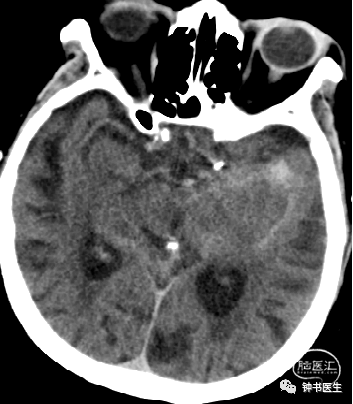

2012-11-8 CT

左颞部脑梗加重,出血渗出点增多。继续加强镇静镇痛治疗。